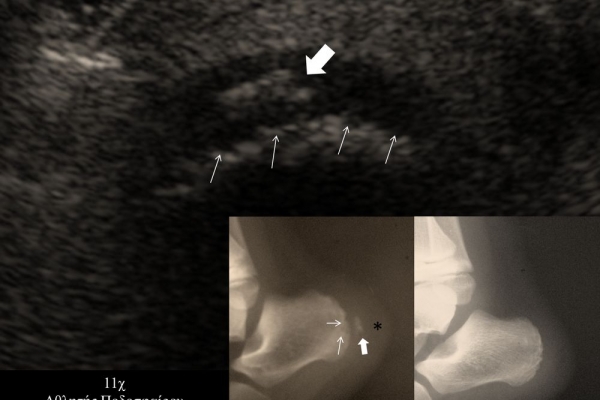

- Παθήσεις Ώμου (πχ ρήξη στροφικού πετάλου)

- Ακρου Ποδός/ Πέλματος (πχ απονευρωσίτιδα)

- Αθλητικές κακώσεις σε παιδιά (πχ αποφυσίτιδα)